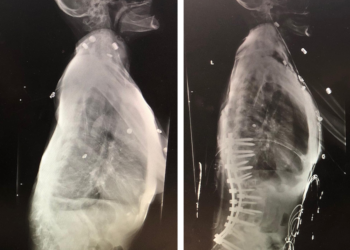

Back:

Revision Surgery Treats Intractable Neck Pain & Cervical Deformity

Author: Benjamin R. Cohen M.D., F.A.A.N.S., F.A.C.S., Read More!

Spine:

Central Cord Syndrome

Author: Yusef Imani M.D., F.A.A.N.S., Read More!

Cervical Laminectomy and Fusion

Author: William Sonstein M.D., F.A.C.S., Read More!

Thoracic Spinal Cord Tumor Case Presentation

Author: Xavier P. J. Gaudin D.O., F.A.C.O.S., Read More!